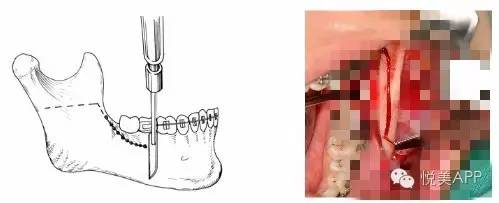

从矢状面劈开下颌支

移动远心骨段之后~固定

固定

检查咬合并固定